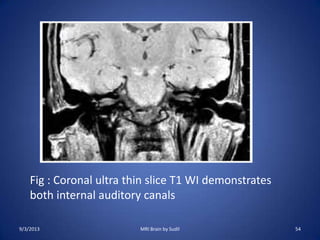

9/3/2013 MRI Brain by Sudil 54

Fig : Coronal ultra thin slice T1 WI demonstrates

both internal auditory canals